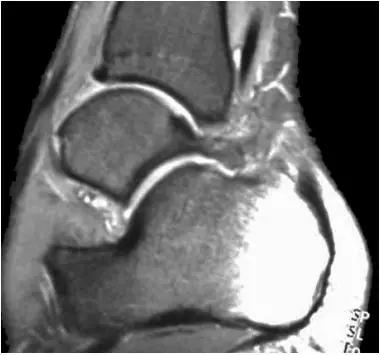

- 又称足球踝,通常为骨性撞击,由于经常性背屈导致胫骨远端关节面前缘与距骨颈部上缘骨赘反复撞击,有时滑膜软骨瘤病的游离体聚积在关节囊前部也会导致前撞击综合症。

- 放射学表现主要为胫骨前下缘与距骨颈部前上缘鸟嘴样骨刺形成。

放射学表现主要为胫骨前下缘与距骨颈部前上缘鸟嘴样骨刺形成